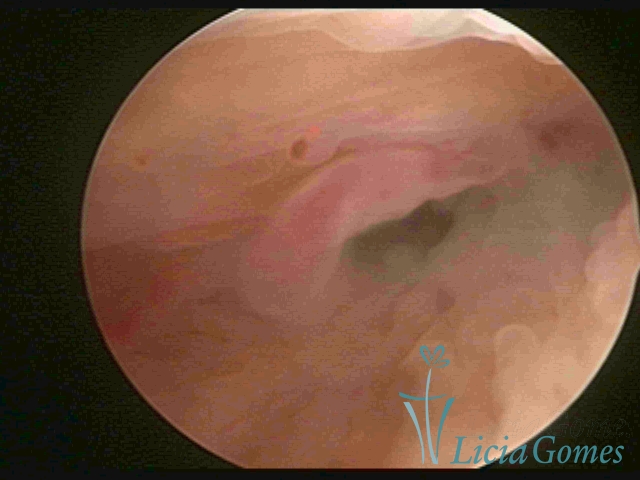

PÓLIPOS ENDOCERVICAIS

São tumores benignos, resultantes da proliferação focal reativa aos processos inflamatórios ou à situações de hiperestrogenismo, e podem ter sésseis (com a base de implantação larga) ou pediculados do epitélio.